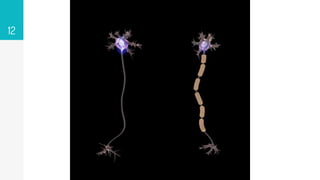

▹ The process of generating myelin is called myelination or

myelinogenesis.

▹ In the CNS, cells called oligodendrocyte precursor cells differentiate

into mature oligodendrocytes, which form myelin.

▹ In humans, myelination begins early in the 3rd trimester, although

only little myelin is present in either the CNS or the PNS at the time

of birth.

▹ During infancy, myelination progresses rapidly, with increasing

numbers of axons acquiring myelin sheaths.

 To increase the speed at which electrical impulses propagate along the

myelinated fibers.

 Myelin decreases capacitance and increases electrical resistance across

the axonal membrane (the axolemma)

 Myelinated fibers lack voltage-gated sodium channels along the

myelinated internodes, exposing them only at the nodes of Ranvier

 Positively charged sodium ions can enter the axon through these voltage-

gated channels, leading to depolarisation of the membrane potential at

the node of Ranvier

FUNCTIONS OF MYELIN SHEATH